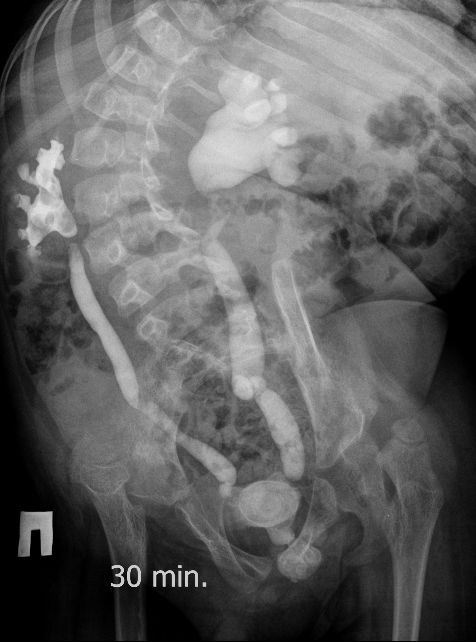

Поскольку откликов нет, добавляю экскреторные урограммы этого же пациента

Нейрогенный мочевой пузырь (?), МКБ, конкремент мочевого пузыря, двухсторонний мегауретер, конкремент правой почки.

И что законтрастировалось на экскреторных урограммах около мочевого пузыря?

DX0004.jpg

Стриктура уретры с расширением ее проксимального отдела?

Если честно, и я изначально не совсем понял, где находится конкремент (а это конечно же конкремент), локализованный на урограммах. При первичном исследовании на УЗИ его я не видел (либо он спрятался за тенью конкремента мочевого пузыря, либо я обрадовался редкой находке конкремента такого размера в мочевом пузыре - 2.5 см, и не посмотрел что ниже). Тем не менее при ретроспективном анализе архивированных сонограмм, как мне кажется, он попал в один из сканов, м.б. не совсем чётко.

И всё -же, где конкремент :?:

Возможно, в дивертикуле либо в нижней трети мочеточника..

Верификация:

Выдержка из протокола операции- "...вскрыт мочевой пузырь, обнаружен камень 4 х 3х 2.5 см, плотный, удалён. При дальнейшей ревизии мочевого пузыря обнаружен вколоченный камень в шейке мочевого пузыря и в уретре, удалён камень 2 х 1.5 х 1.5 см. При осмотре устья левого мочеточника - последний зияет, мочеточник расширен до 1 см, учитывая расширение мочеточника, проведена антирефлюксная пластика по Грегуару..."

На экскреторной урограмме - размеры собирательной системы левой почки уменьшились. Визуализирована расшиенная контрастированная проксимальная уретра.